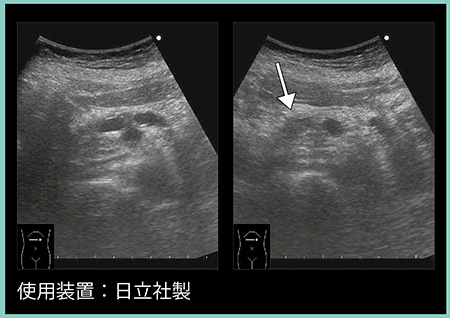

症例3は,62歳,男性。2年前の検診では異常なしであったが(図5 a),検診の超音波検査で膵体部主膵管の拡張と腫瘤を認めた(図5 b↓)。CTでは同部位は造影不良の低吸収域を認め(図6 a↑),MRCPにて体部膵管の狭窄と尾側膵管の拡張を認めたため(図6 b),外科的切除を行った。病理学的には浸潤性膵癌で,T1N1M0,ステージⅡBであった。

図5 症例3:検診発見膵癌の超音波画像